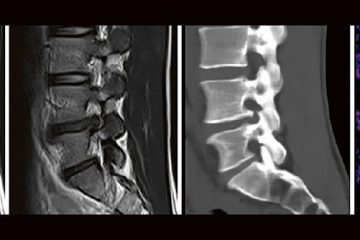

Die technischen Fortschritte bei der Entwicklung neuer Ultraschallgeräte (hochfrequente Ultrabreitband-Linearschallköpfe, Matrixsonden, Verfahren zur Beurteilung der Mikrovaskularisation) sowie Verbesserungen bei der Darstellung von Punktionsnadeln haben in den Gebietender Neurologie, Schmerztherapie, Unfallchirurgie/Orthopädie und Anästhesiologie in den letzten Jahren die Anwendungsbereiche der hochfrequenten Sonographie erheblich erweitert. Unser Anwenderseminar, welches zum 5. Mal ausgerichtet wird, Weiterlesen…